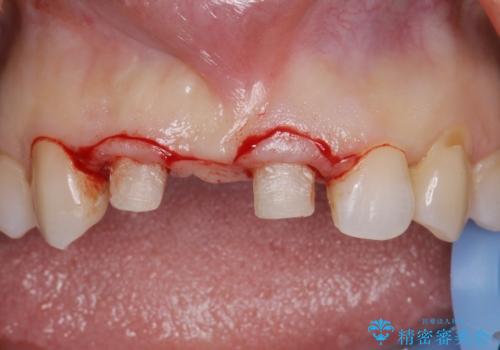

根管治療を行ったのち、歯周外科を行うことで、欠損部の歯ぐきの厚みを出し、縁上歯質を獲得することで、長期的な予後の見込めるブリッジを製作できる環境を整備していきます。

歯周外科をおこなったことで歯ぐきのラインを整え、脱離しないような前歯のブリッジを作製することができました。